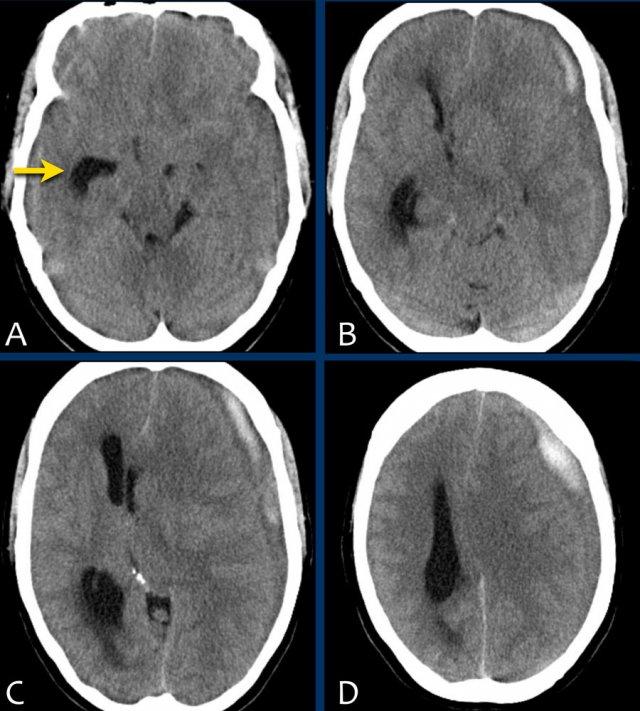

Bé trai 11 tuổi ngã khỏi xe đạp, có thể do cơn co giật động kinh.

Bé đập đầu vào lề đường.

Mức độ ý thức giảm với điểm EMV là 2-4-3.

Bệnh nhân biểu hiện nhịp tim chậm, tăng huyết áp, tư thế bất thường và đồng tử phải giãn không phản xạ ánh sáng — tất cả đều là dấu hiệu của thoát vị não và tăng áp lực nội sọ.

Hình ảnh CT

- Ghi nhận khối xuất huyết hình thấu kính vùng thái dương-đỉnh

- Khối xuất huyết bị giới hạn bởi các đường khớp sọ

- Gãy xương sọ kèm theo

- Dấu hiệu xoáy (swirl sign) cho thấy sự thoát mạch của máu vào trong khối tụ máu. Dấu hiệu này đại diện cho máu tươi chưa đông (giảm tỷ trọng) bao quanh bởi máu đã đông (tăng tỷ trọng hơn).

- Thoát vị dưới liềm não theo chiều ngang và thoát vị móc hải mã.

Bệnh nhân sau đó được phẫu thuật mở hộp sọ và động mạch màng não giữa bị rách đã được đốt cầm máu.

Kết quả lâm sàng tốt.